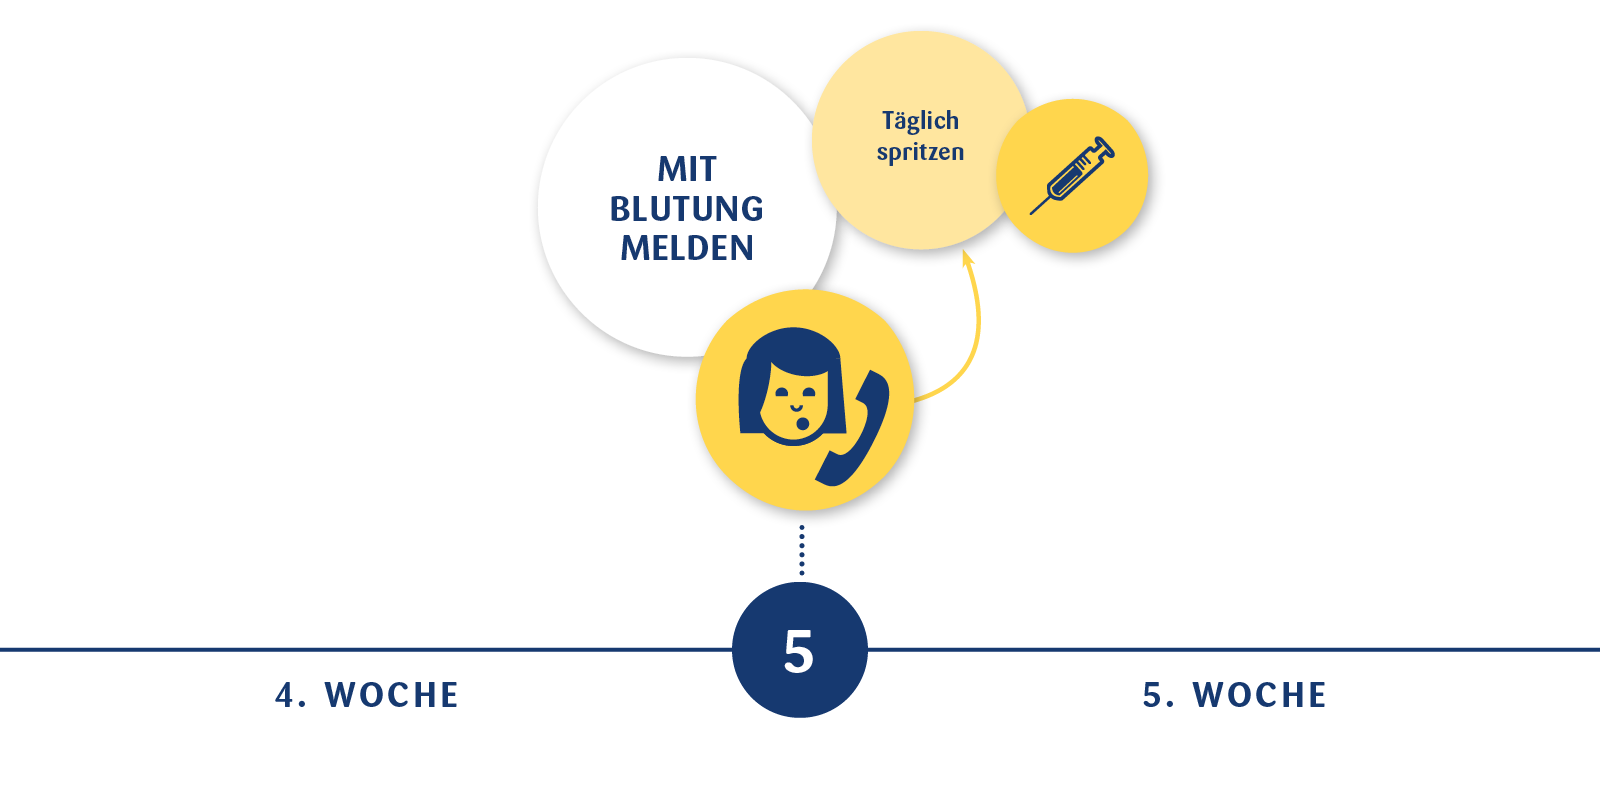

Günü menogon başlıcaz hayırlısıyla başlamadan önce kullananlardan bilgi almak istedim süreç hakkında çiko kistim var bide daha önce klomenden kalan erimek üzere olan minik bir kist de var dr önemli değil başlayabiliriz dedi ama tekrar büyütmesinden korkuyorum.

Menogon kullanýp hamile kalanlar. Yumurtlama ilacıyla hamile kalanlar yumurtlama ilacı nedir yumurtlama ilacıyla nasıl hamile kalınır yumurtlama tedavisi yumurtlama tedavisi ve hamilelik hakkında bilgiler yumurtama ilaçları yanlız size uzman doktorunuzun reteçe ile verilen ve bir yıldır hamile kalamayan kadınlar için önerilen bir yoludur. Merhaba herkese ben de pko var yumurtalarımı büyütmek için iğne tedavisi görmeye başladım i̇lk olarak gonal f 900 alıp 75 doz kullandım ve yumurtam 23 mm oldu çatladı fakat hamıle kalamadım bu ay menogon kullanmaya başlayacağım hsg çekildim temiz çıktı doktorum. Merhaba canım bende klomen ve çatlatma iğnesi ile hamile kaldım. 12 şubat 2014 başarısız tüp bebek denemeleri.

Tüp bebek neden tutmaz. Canım ben de menogon iğne ve klomen kullandım sadece 3 yumurtam oluşmuş çatlatma iğnesi verdi bugün olucam ertesi gün için aşılama dedi ama eşim aşılamayı istemiyor bizde kendimiz deniycez senin nasıl oldu bilgi verir misin. En az 3 tüp bebek tedavi girişiminde iyi kalitedeki embriyo transfer edilmesine karşın hamilelik oluşmaması ya da toplamda 10 ya da daha fazla embriyonun transferine rağmen hamilelik elde edilememesi tekrarlayan tüp bebek başarısızlığı diye adlandırılan bir durumdur. Mrb arkadaşlar menogon kullanan var mı ben ilk defa bu ay başladım daha 1 tane vuruldum bu iğneyle kaçıncı günde büyüdü yumurtalarınız ve bu yolla hamile kalanlar var mı forumlara baktım ama hep eski tarihli bende yeni bir konuda açmak istedim lütfen kullananlar bu forumda buluşalım.

Tüp bebek tedavilerinde hedeflenen nokta istenilen sayıda ve istenilen kalitede embriyo elde etmektir. Tüp bebek tedavisinde amaç. Tüp bebek kadına veya erkeğe bağlı kısırlık sebebiyle çocuk sahibi olamayan anne baba adaylarına uygulanan yardımcı üreme tekniğine verilen addır. Yumurtalıklar hap serophene gonaphene klomid klomen veya gonadotropin gonal f puregon menogon menopur fostimon merional adı verilen iğneler ile uyarılabilir.

Canımlar adetime az kaldı 3. İğne ile yapılan uyarıda daha fazla yumurta elde edildiğinden ve hapların rahim iç tabakası üzerine potansiyel olumsuz etkilerinden dolayı daha yüksek gebelik. Gonal f ve menogon kullanıp hamile kalanlar var mı. Kadından yumurta toplama ile elde edilen yumurta ve erkekten alınan spermin laboratuvar ortamında birleştirilmesi döllenmesi sonrası elde edilen embriyonun rahim içine nakledilmesidir.